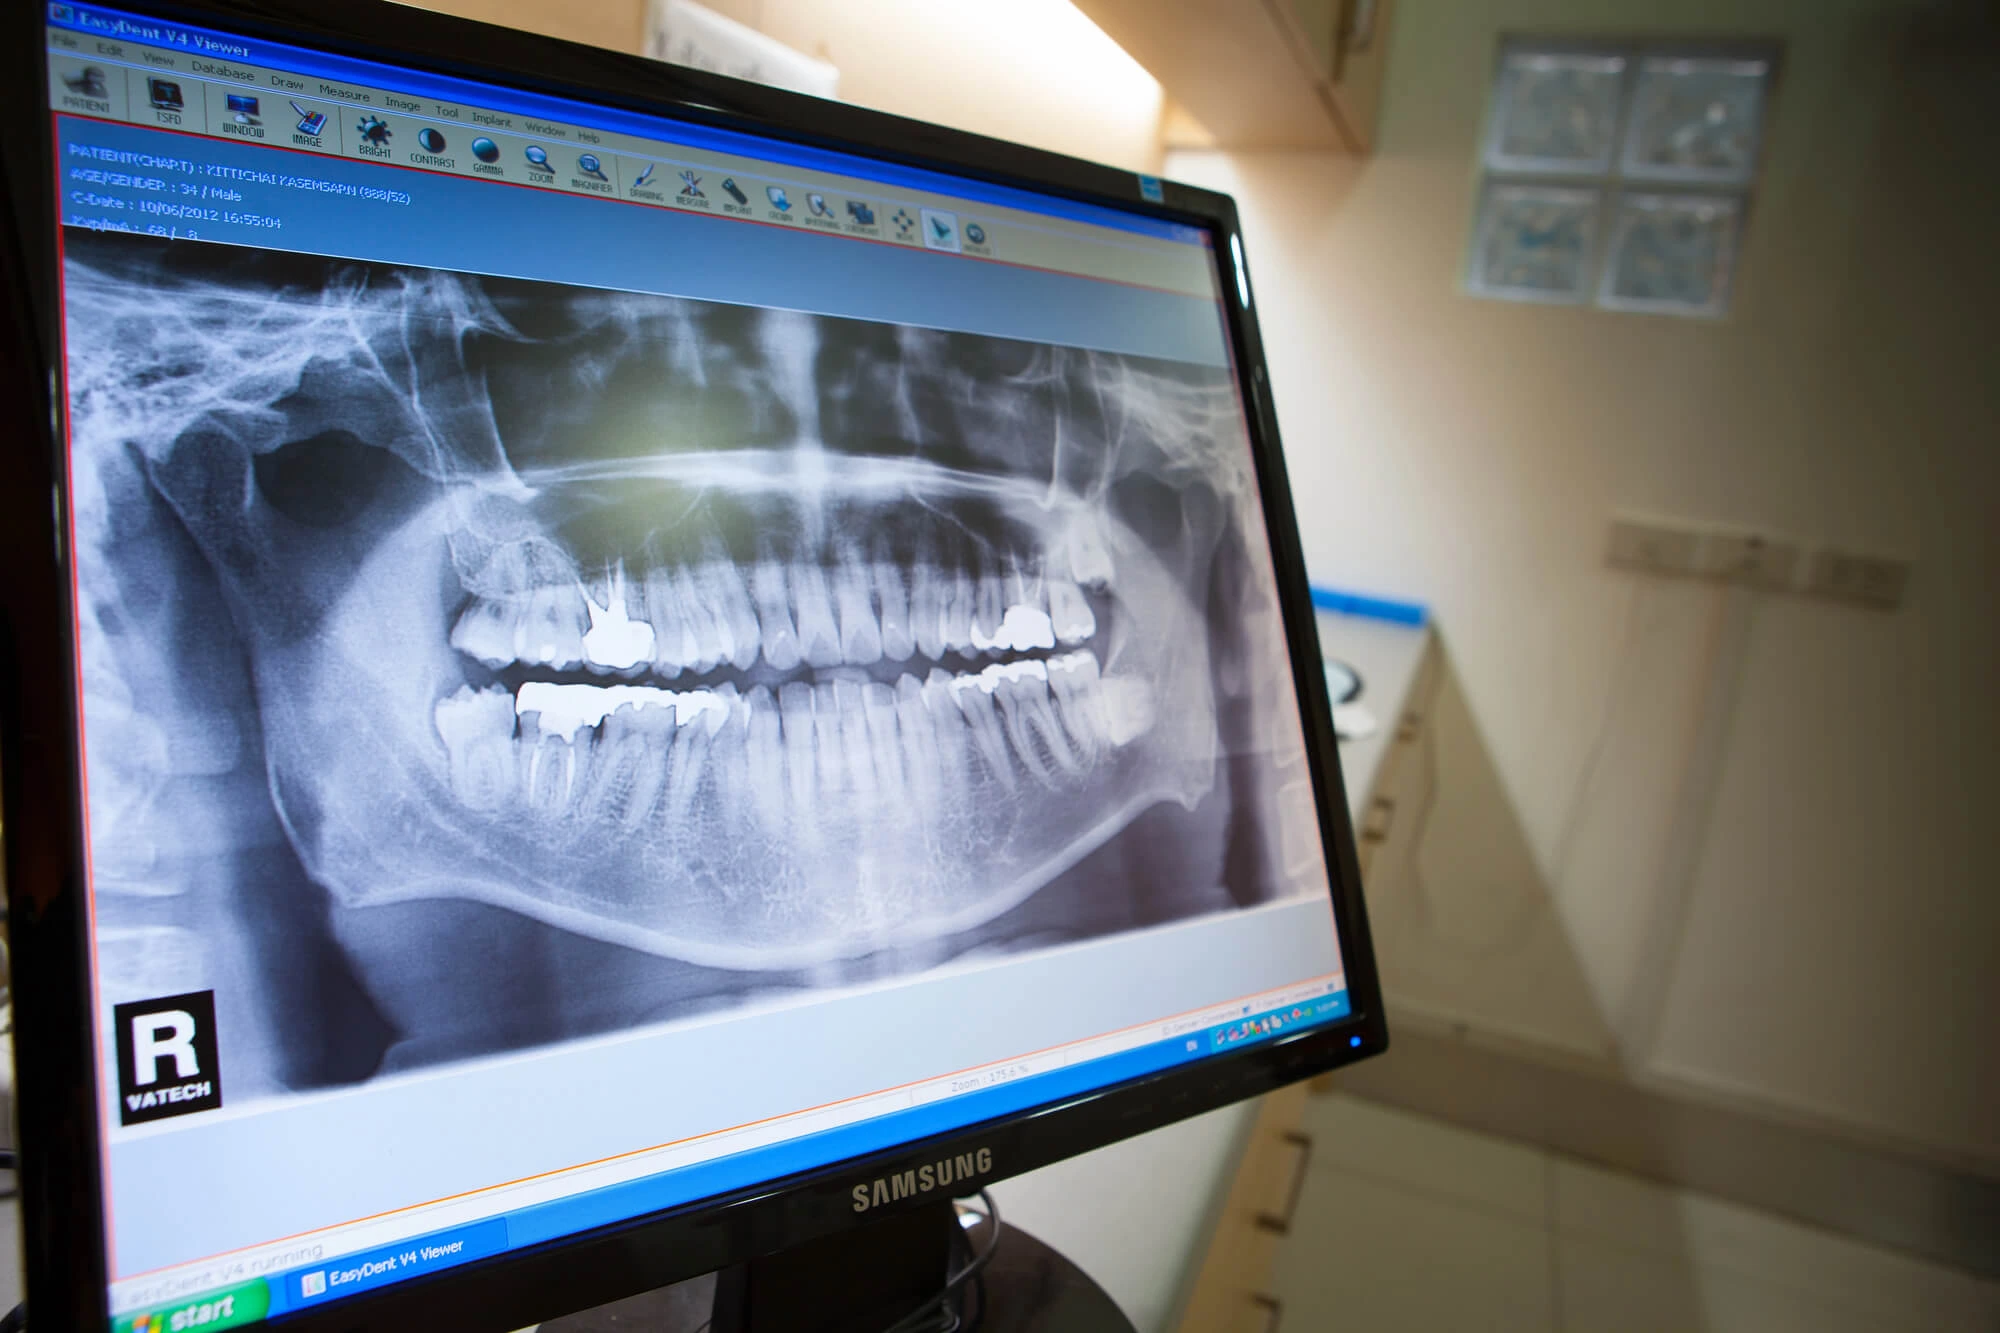

Luckily, it’s never too late to start again. Your dentist will begin with a comprehensive exam to assess your current oral health, check for cavities or gum disease, and take X-rays if needed.